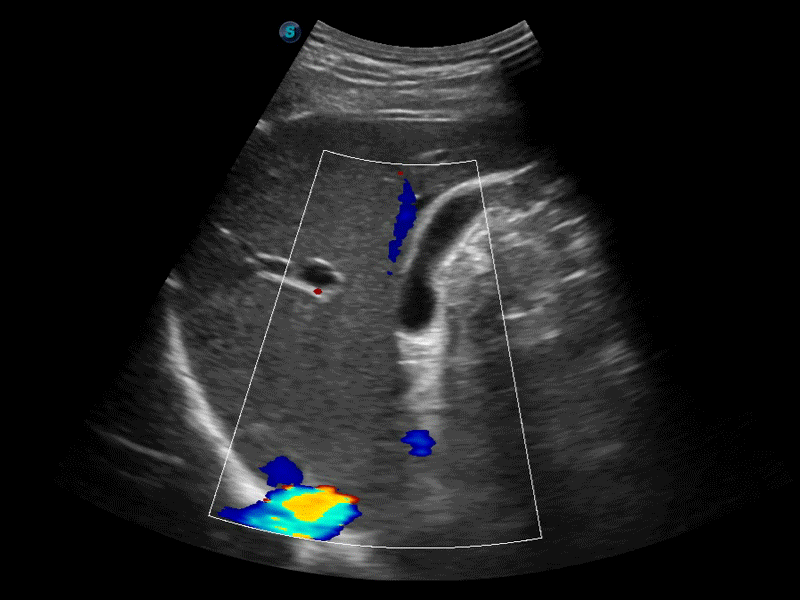

高分辨率血流成像技术提高了对低速血流信号的检测能力。在提高空间分辨率的同时,也克服了血流外溢现象,为用户提供更加真实的血流动力学信息。

通过色彩血流和实时宽景相结合,可观察到完整的静脉或动脉的血流,方便医生检查。实时扫查过程中,如有任何操作失误也可以很容易地进行回扫擦除,而不会中断扫查。